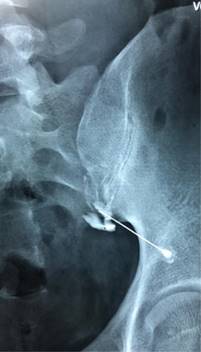

Infiltración diagnóstica: si después de un curso de terapia farmacológica, analgésica y antiinflamatorios no esteroideos los síntomas de la ASI no se han resuelto de manera adecuada, el siguiente paso en el tratamiento por lo general se trata de infiltraciones de la articulación sacroilíaca. El procedimiento es esencialmente diagnóstico más que terapéutico; sin embargo, si se agregan esteroides a los fármacos utilizados, el alivio del dolor se logra por una duración clínicamente relevante, alrededor de cuatro a seis meses. Antes de llevar a cabo una infiltración de la ASI, el nivel de dolor del paciente debe evaluarse usando una escala clínica subjetiva de cero a 10 puntos. La infiltración de la ASI debe ser guiada utilizando imagen fluoroscópica con una cantidad mínima de medio de contraste (Figura 8) para confirmar la colocación de la aguja dentro de la articulación; la razón de que las infiltraciones deban ser guiadas siempre por medio de fluoroscopía es que se ha evidenciado que sólo 12-22% de las infiltraciones logran llegar a la articulación cuando no se realizan guiadas por imagen. Teniendo en cuenta el pequeño tamaño de la articulación, la solución que se utiliza en la infiltración debe incluir una combinación de agentes anestésicos. Después de aproximadamente cuatro horas el nivel del dolor del paciente debe reevaluarse, la mayoría de pacientes muestran un alivio inmediato del dolor, el cual se prolonga hasta por 12 horas y más, se han registrado episodios de dolor sacroilíaco posteriores a las 12 horas, que se han manejado con medicamentos analgésicos y AINES, hielo local y reposo en cama. Se considera la infiltración exitosa y adecuada si el dolor del paciente se reduce al menos en 75% del nivel presentado en la evaluación inicial. Estudios recientes consideran que un alivio de 50% podría ser suficiente para diagnóstico.2,4,5,15,16,17